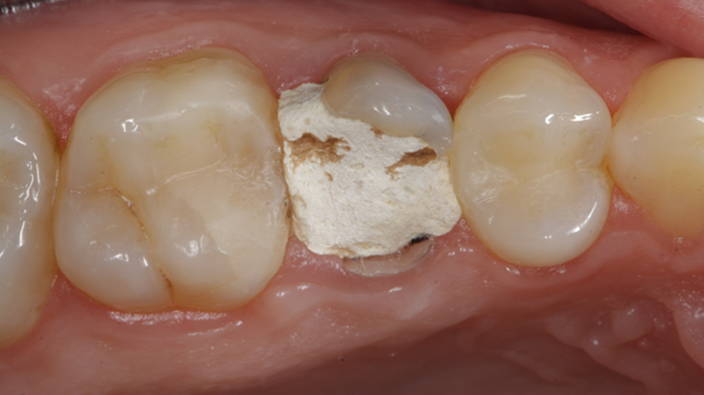

Clinical case: Extraction, immediate implant placement, & provisionalization

- Courtesy of Dr. Iulian Filipov, Romania -

Keywords

AnyRidge, R2GATE, guided surgery, immediate placement, immediate provisionalization, initial stability, Dr. Iulian Filipov, #25, maxillary posterior, immediate loading, Mega ISQ